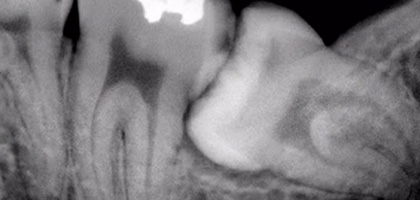

1. 칫솔이 잘 닿지 않아 사랑니 자체가 썩는 경우 사랑니 주변 잇몸에 염증이 발생하며 잇몸과 볼이 붓게 됩니다.

2. 누워있는 사랑니의 인접 어금니(제2대구치)의 충치를 유발하게 됩니다.